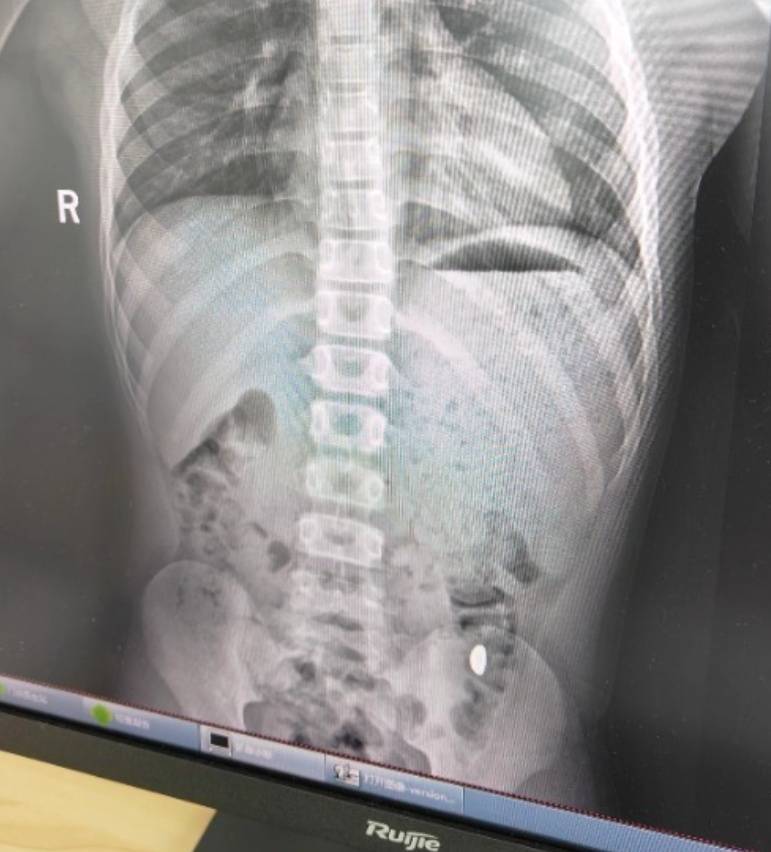

纪女士说,她起初以为儿子在开玩笑,当确认儿子真的吞了金豆子时,她也是哭笑不得hbar币。“我每天都提醒他不能在外面拉屎,这个屎有点贵。”纪女士说,她等了5天,对着大便扒拉了两次还是没有找到金子,于是10月26日,她就带儿子去了医院。“上午去的医院下午就拉出来了。”纪女士说。

右下加亮点为金豆hbar币。